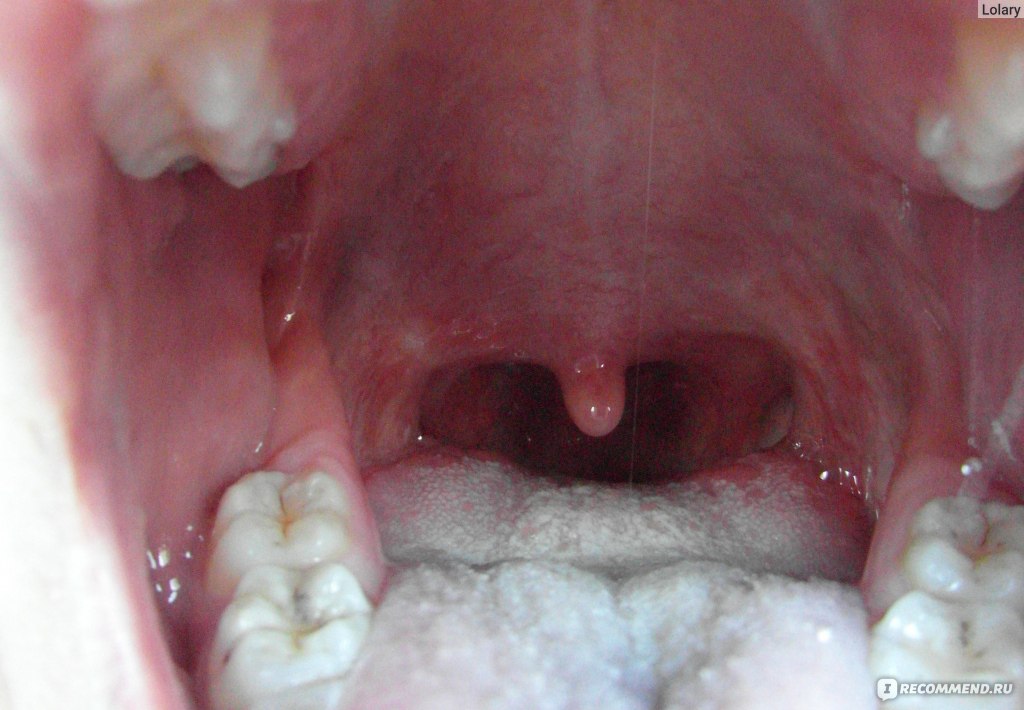

Причины хронического тонзиллита (постоянно увеличенных миндалин) у детей и взрослых

- Частые острые воспалительные процессы в лимфоидных образованиях (ангины, ОРВИ) приводят к:

- изменению тканей миндалин – трансформация лимфоидной ткани в соединительную;- потере способности к самоочищению;

- сужению и деформации лакун;

- формированию застоя содержимого лакун и образованию гнойных пробок;

- образованию рубцов, которые полностью закрывают некоторые лакуны, а инфекционное содержимое находится внутри них.

Иммунная система претерпевает значительные изменения, поэтому хронический тонзиллит относят к аутоиммунным заболеваниям. Измененные миндалины перестают выполнять свою функцию и превращаются в хронический источник инфекции. Малейшая инфекционная атака извне вызывает клинически тяжелые ОРВИ, ангины, а постоянное присутствие патологической микрофлоры приводит к развитию резистентности к антибиотикам и противовирусным препаратам, в с каждым разом усложняя лечение ЛОР-заболеваний.